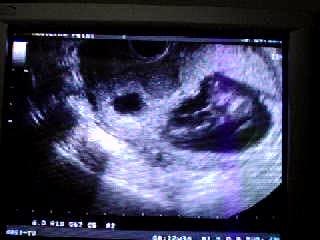

Ecografía Semana 22 (I)

Primera parte da ecografía de la 22 semana